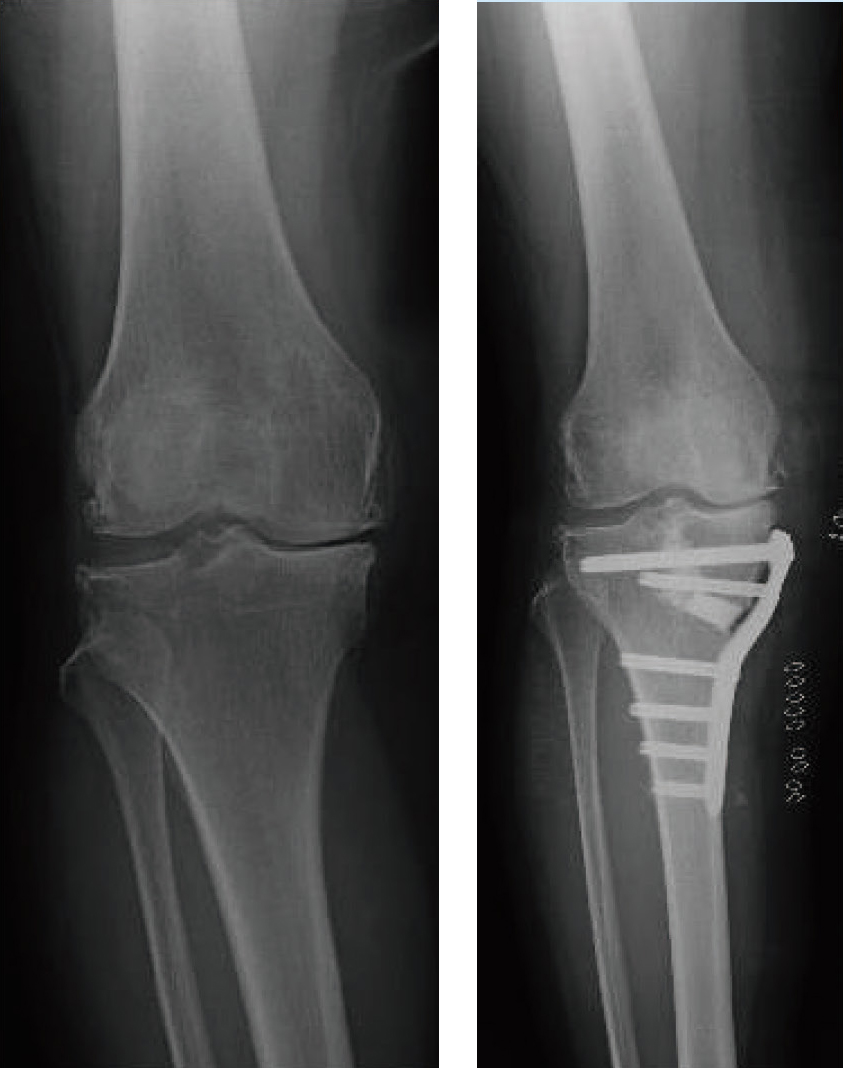

術前 術後

脛骨顆外反骨切り術(TCVO)のレントゲン

膝周囲骨切り術(AKO、上)と

高位脛骨骨切り術(HTO、下)

骨を切り膝にかかる荷重の位置を変える手術を骨切り術というのですが、その方法にはいくつかあります。膝の周囲で骨を切って、脚の形を矯正する手術を膝周囲骨切り術(AKO)。脛骨を切ってO脚変形をまっすぐ、あるいは軽度のX 脚に矯正する高位脛骨骨切り術(HTO)や、シーソー膝(関節の外側も内側もグラグラで不安定な膝)を安定させO脚も矯正できる脛骨顆外反骨切り術(TCVO)などがあります。

骨が癒合し、プレートを抜去するまでは多少の痛みが残りますが、自分の関節が温存されるので動作の制限はほとんどありません。スポーツも可能です。また、脚の形が自然になることで、見た目も歩き方も綺麗になります。手術方法や、骨を固定する材料の進化により、以前に比べて入院期間も短くなっています。